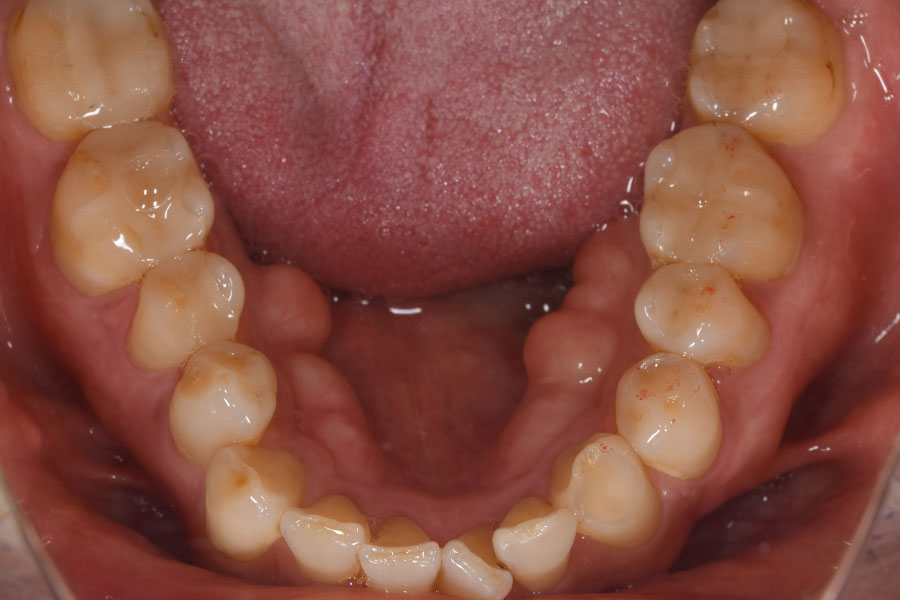

Before -下顎-

| 施術内容 | 金属アレルギー予防を目的に、金属フリーの自費補綴へ変更。適合性・清掃性・審美性の向上が得られています。 |

|---|---|

| 治療期間 | 約4ヶ月 |

| 費用 | オールセラミックインレー 693,000円 |

| リスク・副作用 | 治療にともない、歯の破折や歯質の削合、場合によっては抜歯が必要となることがあります。また、金属や補綴物を除去する際に、完全に除去できない場合もあります。 |